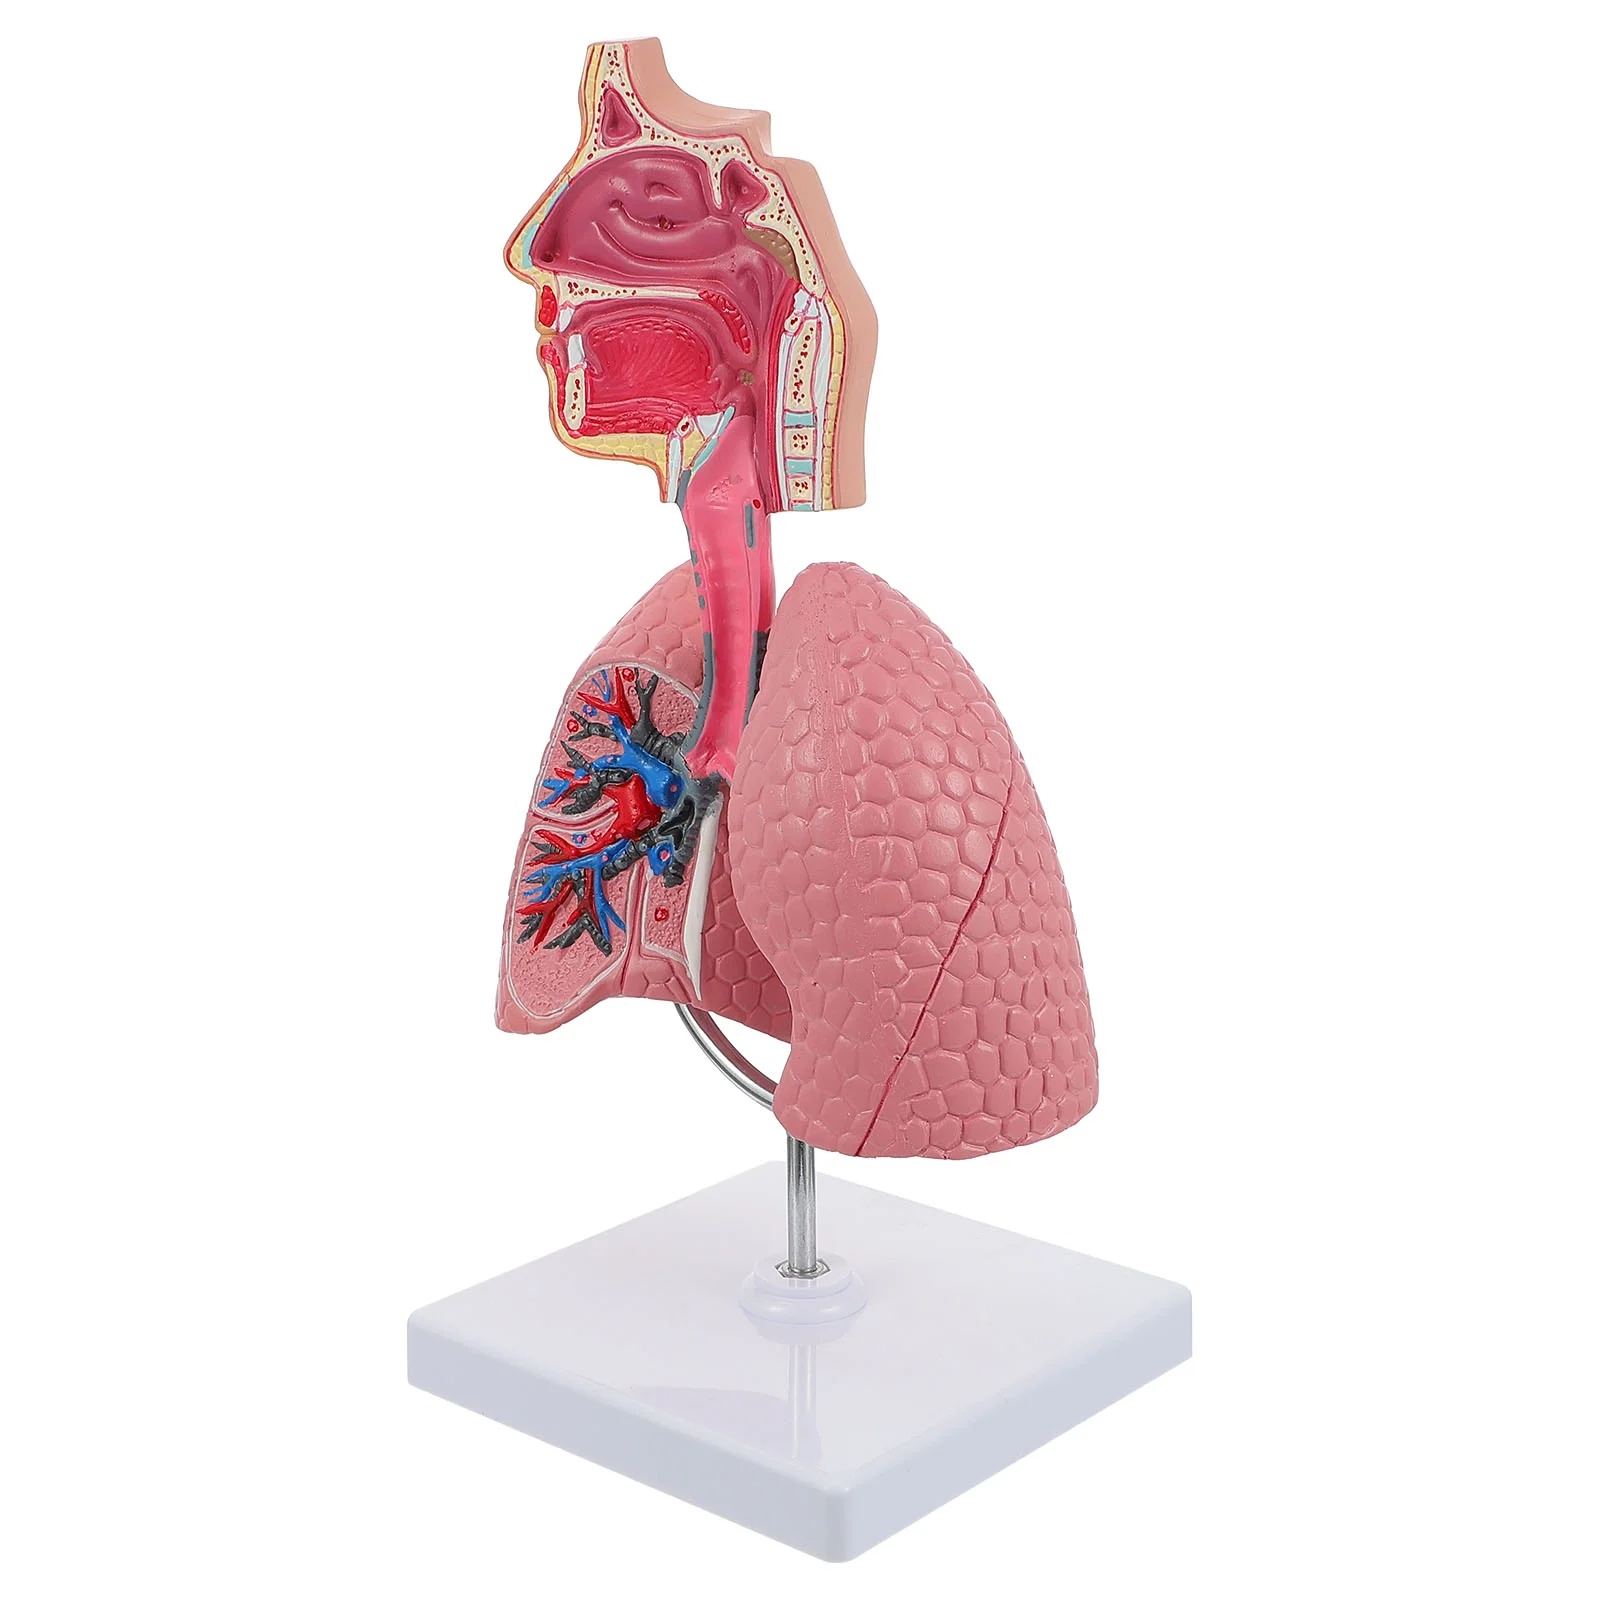

M17F Life Size Human Lung Model Anatomical Respiratory System Anatomy Teaching Tool

Lung Respiratory Anatomy Model Teaching System Human Display model School Lungs Anatomical Heart Educational Nasal Toy

Lung Respiratory Anatomy Model Teaching System Human Display model School Lungs Anatomical Heart Educational Nasal Toy

Lung Respiratory Anatomy Model Teaching System Human Display model School Lungs Anatomical Heart Educational Nasal Toy

Lung Respiratory Anatomy Model Teaching System Human Display model School Lungs Anatomical Heart Educational Nasal Toy

PVC Respiratory System Model Lifelike Teaching Aid for Medical Schools Anatomy Education Practical Human Lung Display Tool